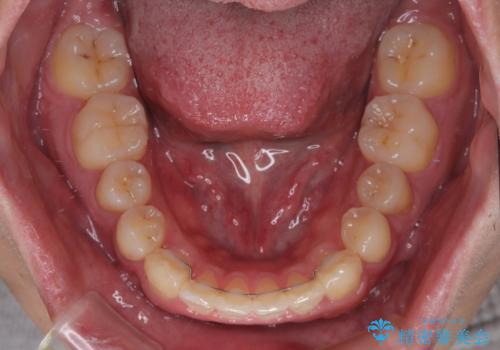

舌突出癖が改善されず、なかなか正中の隙間や上下の前歯が接触しなかったために治療が長期化してしまいました。

また、治療期間中のプラークコントロールが悪く、ブラッシング指導も奏功しなかったため、装置の周りが脱灰した状態(初期むし歯)となってしまいました。